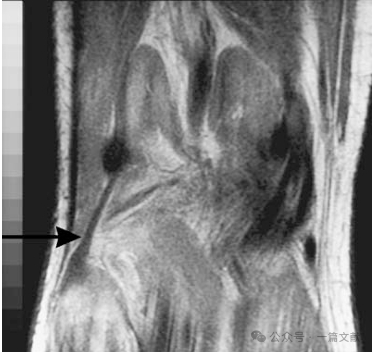

3.腘斜韧带:右膝后侧观显示腘斜韧带(OPL)。其内侧由后斜韧带(POL)的关节囊支与半膜肌(SM)总腱的侧向腱性扩展部融合构成;外侧则附着于腓肠豆区域的关节囊及跖肌止点处(箭头所示)。(注:已移除腓肠肌内外侧头,跖肌保留原位)。